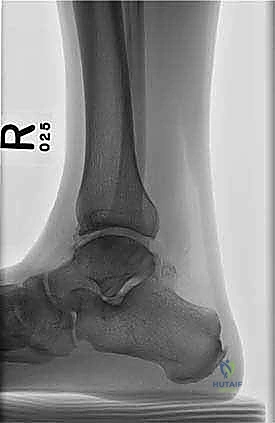

- التصوير بالأشعة السينية (X-rays): الخطوة الأولى لاستبعاد الكسور الكبيرة وتقييم المحاذاة العامة للعظام. قد تظهر الأشعة السينية الآفات الكبيرة، لكنها غالباً ما تفشل في إظهار التلف الغضروفي المبكر.

- التصوير بالرنين المغناطيسي (MRI): هو "المعيار الذهبي" لتشخيص آفات الكاحل. يوضح الرنين المغناطيسي بدقة متناهية حالة الغضروف، حجم التكيسات العظمية، ومقدار التورم داخل العظم (Bone marrow edema). من خلال صور الرنين، يحدد الدكتور هطيف أبعاد الآفة (الطول، العرض، العمق) بدقة المليمتر.

- التصوير المقطعي المحوسب (CT Scan): ضروري جداً للآفات الكبيرة. يوفر الـ CT صورة ثلاثية الأبعاد للعظم، مما يساعد الجراح في التخطيط الدقيق لعملية قطع العظم وحجم الطعم المطلوب زراعته.